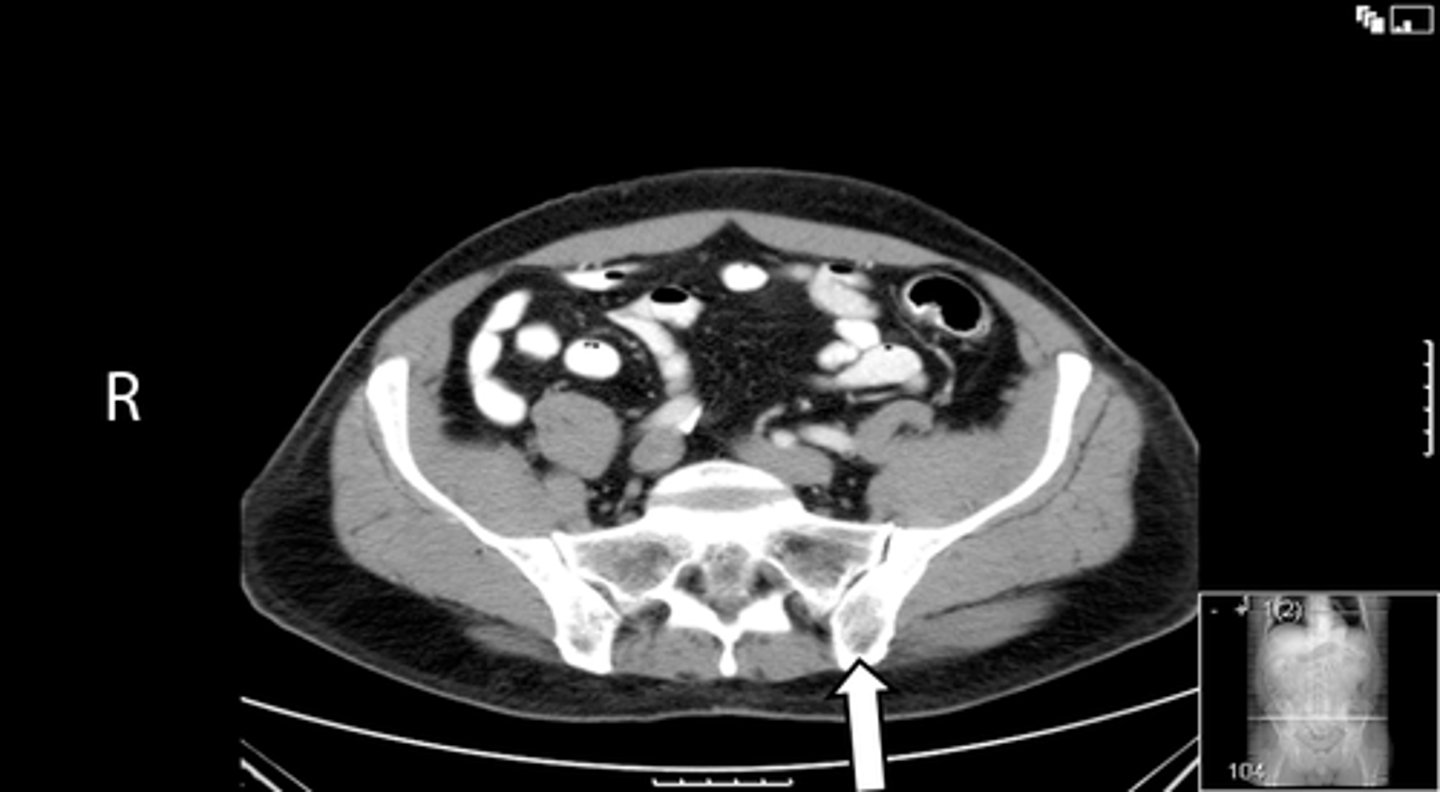

<p>What is indicated in the image?</p>

Axial male pelvis CT

What is the image?

<p>What is the image?</p>

Aorta

Cecum

IVC

L ilium

L psoas muscle

R ilium

R psoas muscle

R rectus abdominis

Terminal ilium